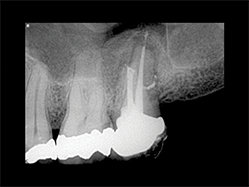

Slika 5:Prikazuje slučaj pogodan za reviziju punjenja s obzirom na loš rezulatat prethodne terapije kanala korena. Uz odgovarajuću obradu i irigaciju(Sleimanova faza) i zahvaljujući teškoj ali uspešnoj potrazi za distalnim kanalom, izvršena je 3-D opturacija kanala koja pokazuje suženje između mezijalnog i distalnog kanala kao i veoma visoko postavljene lateralne kanaliće u palatinalnom kanalu.